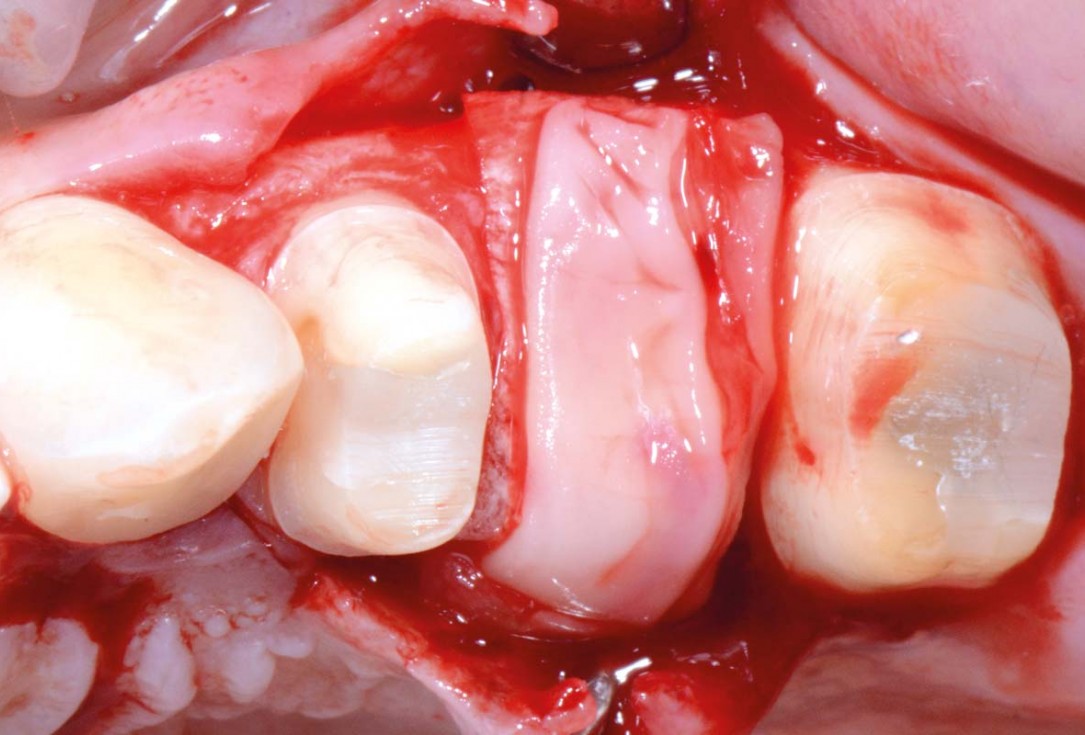

03/16 - Jason® membrane placed as palatal “wall” supporting the allogenic granules (maxgraft®)Full bone regeneration in extraction socket augmented with maxgraft® and Jason® membrane – Dr. C. Landsberg